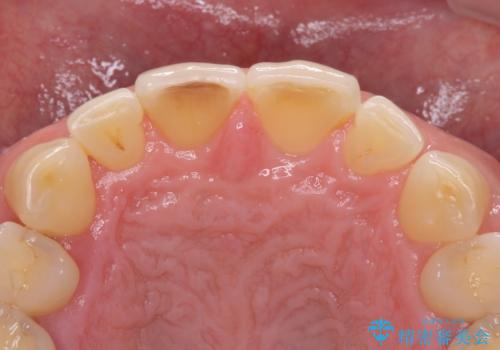

- 前歯の目立つ隙間を気にして来院された患者様です。

高校生の頃に矯正治療を行ったものの、強い咬合力により上顎が拡大され、正中に隙間ができてしまいました。

通常では歯の周囲全体を削った上でクラウンを装着することが多いのですが、咬合力が非常に強く、クラウンではセラミックが欠けてしまう可能性が考えられたため、咬合を変えることとのないラミネートベニアにて治療を行うこととしました。